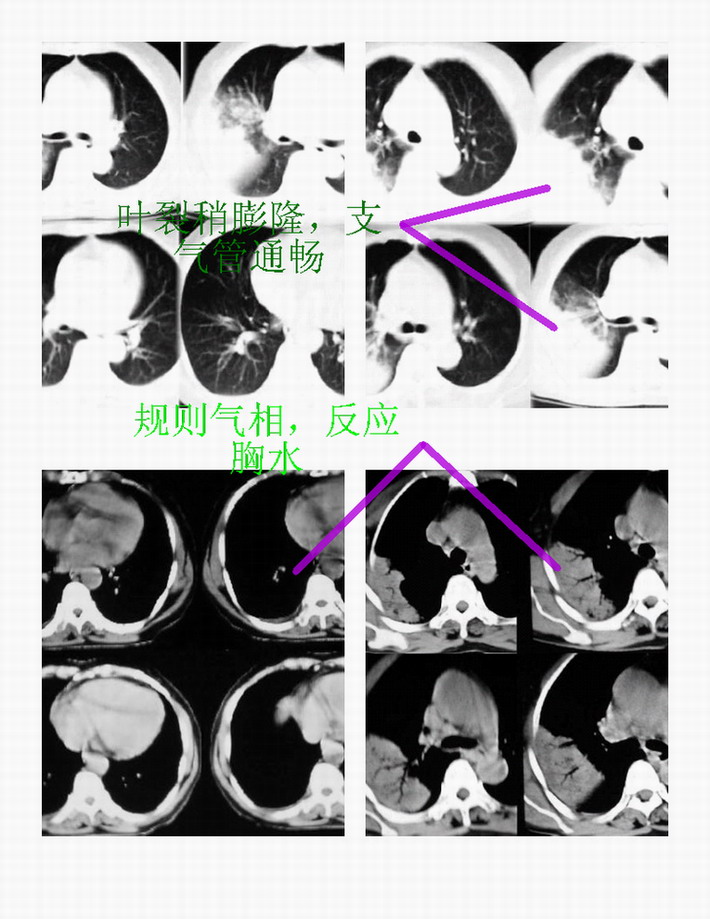

右上叶后段见大片状实变阴影,见含气支气管征,近肺门见支气管血管束增粗,上腔静脉后见小淋巴结. 后胸膜腔见少量积液. 印象:1,大叶性肺炎.2,节段性肺炎<混合菌感染>.3.建议抗炎后复查待除外其他病变

应该是大叶性肺炎,下袁平直,且见空气支气管,分支清楚,没有枯树枝那种改变

右肺上叶肺实变,内见①支气管气像②边缘模糊③叶间裂稍饱满这些都是支持肺炎的证据。尤其是边缘模糊,其病理学依据是炎症渗出性物质通过肺泡间孔和/或呼吸性细支气管向临近的肺组织蔓延渗透,和其他表现在一起成为诊断肺炎的重要表现。

右肺上叶尖后段大片扇形实变影,边缘略呈云片状渗出。并见“支气管气相”,结合病史支持大叶性肺炎诊断。建议正规抗炎复查。

大叶性肺炎,右侧少量反应性胸水